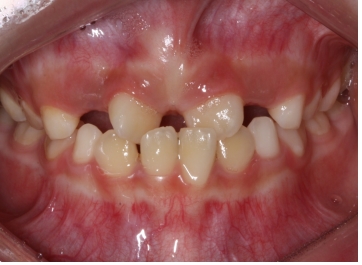

¾Õ´Ï°¡ ¹ú¾îÁö°í »ß¶Ô¾îÁ® Àִ ȯÀÚ¿¡¼ X-ray¸¦ ÃÔ¿µÇÏ¿´´õ´Ï °úÀ×Ä¡°¡ ¸Åº¹µÇ¾î ÀÖ´Â °ÍÀÌ º¸ÀÔ´Ï´Ù.

Ä¡¾Æ »Ñ¸® ¾ÕÂÊ¿¡ ¸Åº¹µÇ¾î ÀÖ´Â °úÀ×Ä¡·Î ÀÎÇØ ¾Õ´Ï »çÀ̰¡ ¹ú¾îÁö°í, ¿À¸¥ÂÊ ¾Õ´Ï°¡ »ß¶Ô¾îÁø ä·Î

¸ÍÃâÇÏ¿´½À´Ï´Ù.

ÀÌ·± °æ¿ì °úÀ×Ä¡¸¦ ¹ßÄ¡ÇÏ°í °£´ÜÇÑ ±³Á¤Ä¡·á·Î ¹®Á¦¸¦ ÇØ°áÇØÁÙ ¼ö ÀÖ½À´Ï´Ù.

¾Õ´Ï»çÀÌ¿¡ À§Ä¡ÇÑ °úÀ×Ä¡ ¶§¹®¿¡ ´Ù¸¥ Ä¡¾ÆµéÀÌ ¸ÍÃâÇÒ °ø°£ÀÌ ºÎÁ·ÇØÁ®¼ Ä¡¾Æ°¡ »ß¶Ô¾îÁ³½À´Ï´Ù.